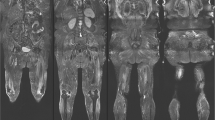

Muscle oedema was most commonly observed in the quadriceps (n = 9, 69.23%) and gluteal muscles (n = 7, 53.85%). The adductor compartment was involved in five patients (38.46%) and the hamstrings in four (30.77%). Seven patients (53.85%) had moderate or severe oedema and notably six such patients had concurrent fascial oedema (see Fig. 1). Patients with severe muscle oedema had multiple muscle groups involved. No patient had isolated fascial oedema.